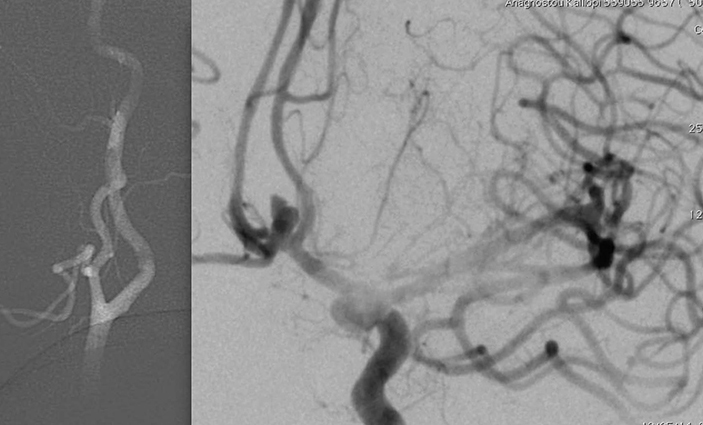

H τεχνική αυτή περιγράφηκε από τον J. Moret (1994) και χρησιμοποιήθηκε σε ανευρύσματα με ευρύ αυχένα, (RSN <1.5), όπου είναι αδύνατο να σχηματισθεί ένα σταθερό πλέγμα των coils, και να παραμείνουν τα coils μέσα στόν σάκκο, με αποτέλεσμα να προπίπτουν στο θυγατρικό αγγείο, με κίνδυνο θρομβώσεως του αγγείου. Σε αυτή την περίπτωση μέσα στο αγγείο προωθούμε δύο καθετήρες.

Ο ένας καθετήρας είναι τό μπαλόνι προστασίας που προωθείται ακριβώς μπροστά από τον αυχένα του ανευρύσματος. Στην συνέχεια ο μικροκαθετήρας εισάγεται μέσα στο ανεύρυσμα. Διαστέλλουμε το μπαλόνι το οποίο λαμβάνει το σχήμα του θυγατρικού αγγείου, γεφυρώνει τον αυχένα, και εμποδίζει την έξοδο των σπειραμάτων, όταν αυτά τοποθετούνται μέσα στο ανεύρυσμα. Με αυτή την τεχνική όχι μόνο γίνεται εφικτός ο εμβολισμός ανευρυσμάτων με ευρύ αυχένα, αλλά επιτυγχάνεται μεγαλύτερη πυκνότητα πληρώσεως του ανευρύσματος με coils. Υπάρχουν στην διάθεση μας μπαλόνια πολύ ευένδοτα (Hyperform and Hyperglide remodelling balloons)

που όταν διαστέλονται προσαρμόζονται κατάλληλα στην ανατομία του αγγείου, ιδιαίτερα σε θέσεις διχασμού ώστε να επιτρέπουν τον αποκλεισμό του αυχένα σε ιδιαίτερα δυσπλαστικά ανευρύσματα).